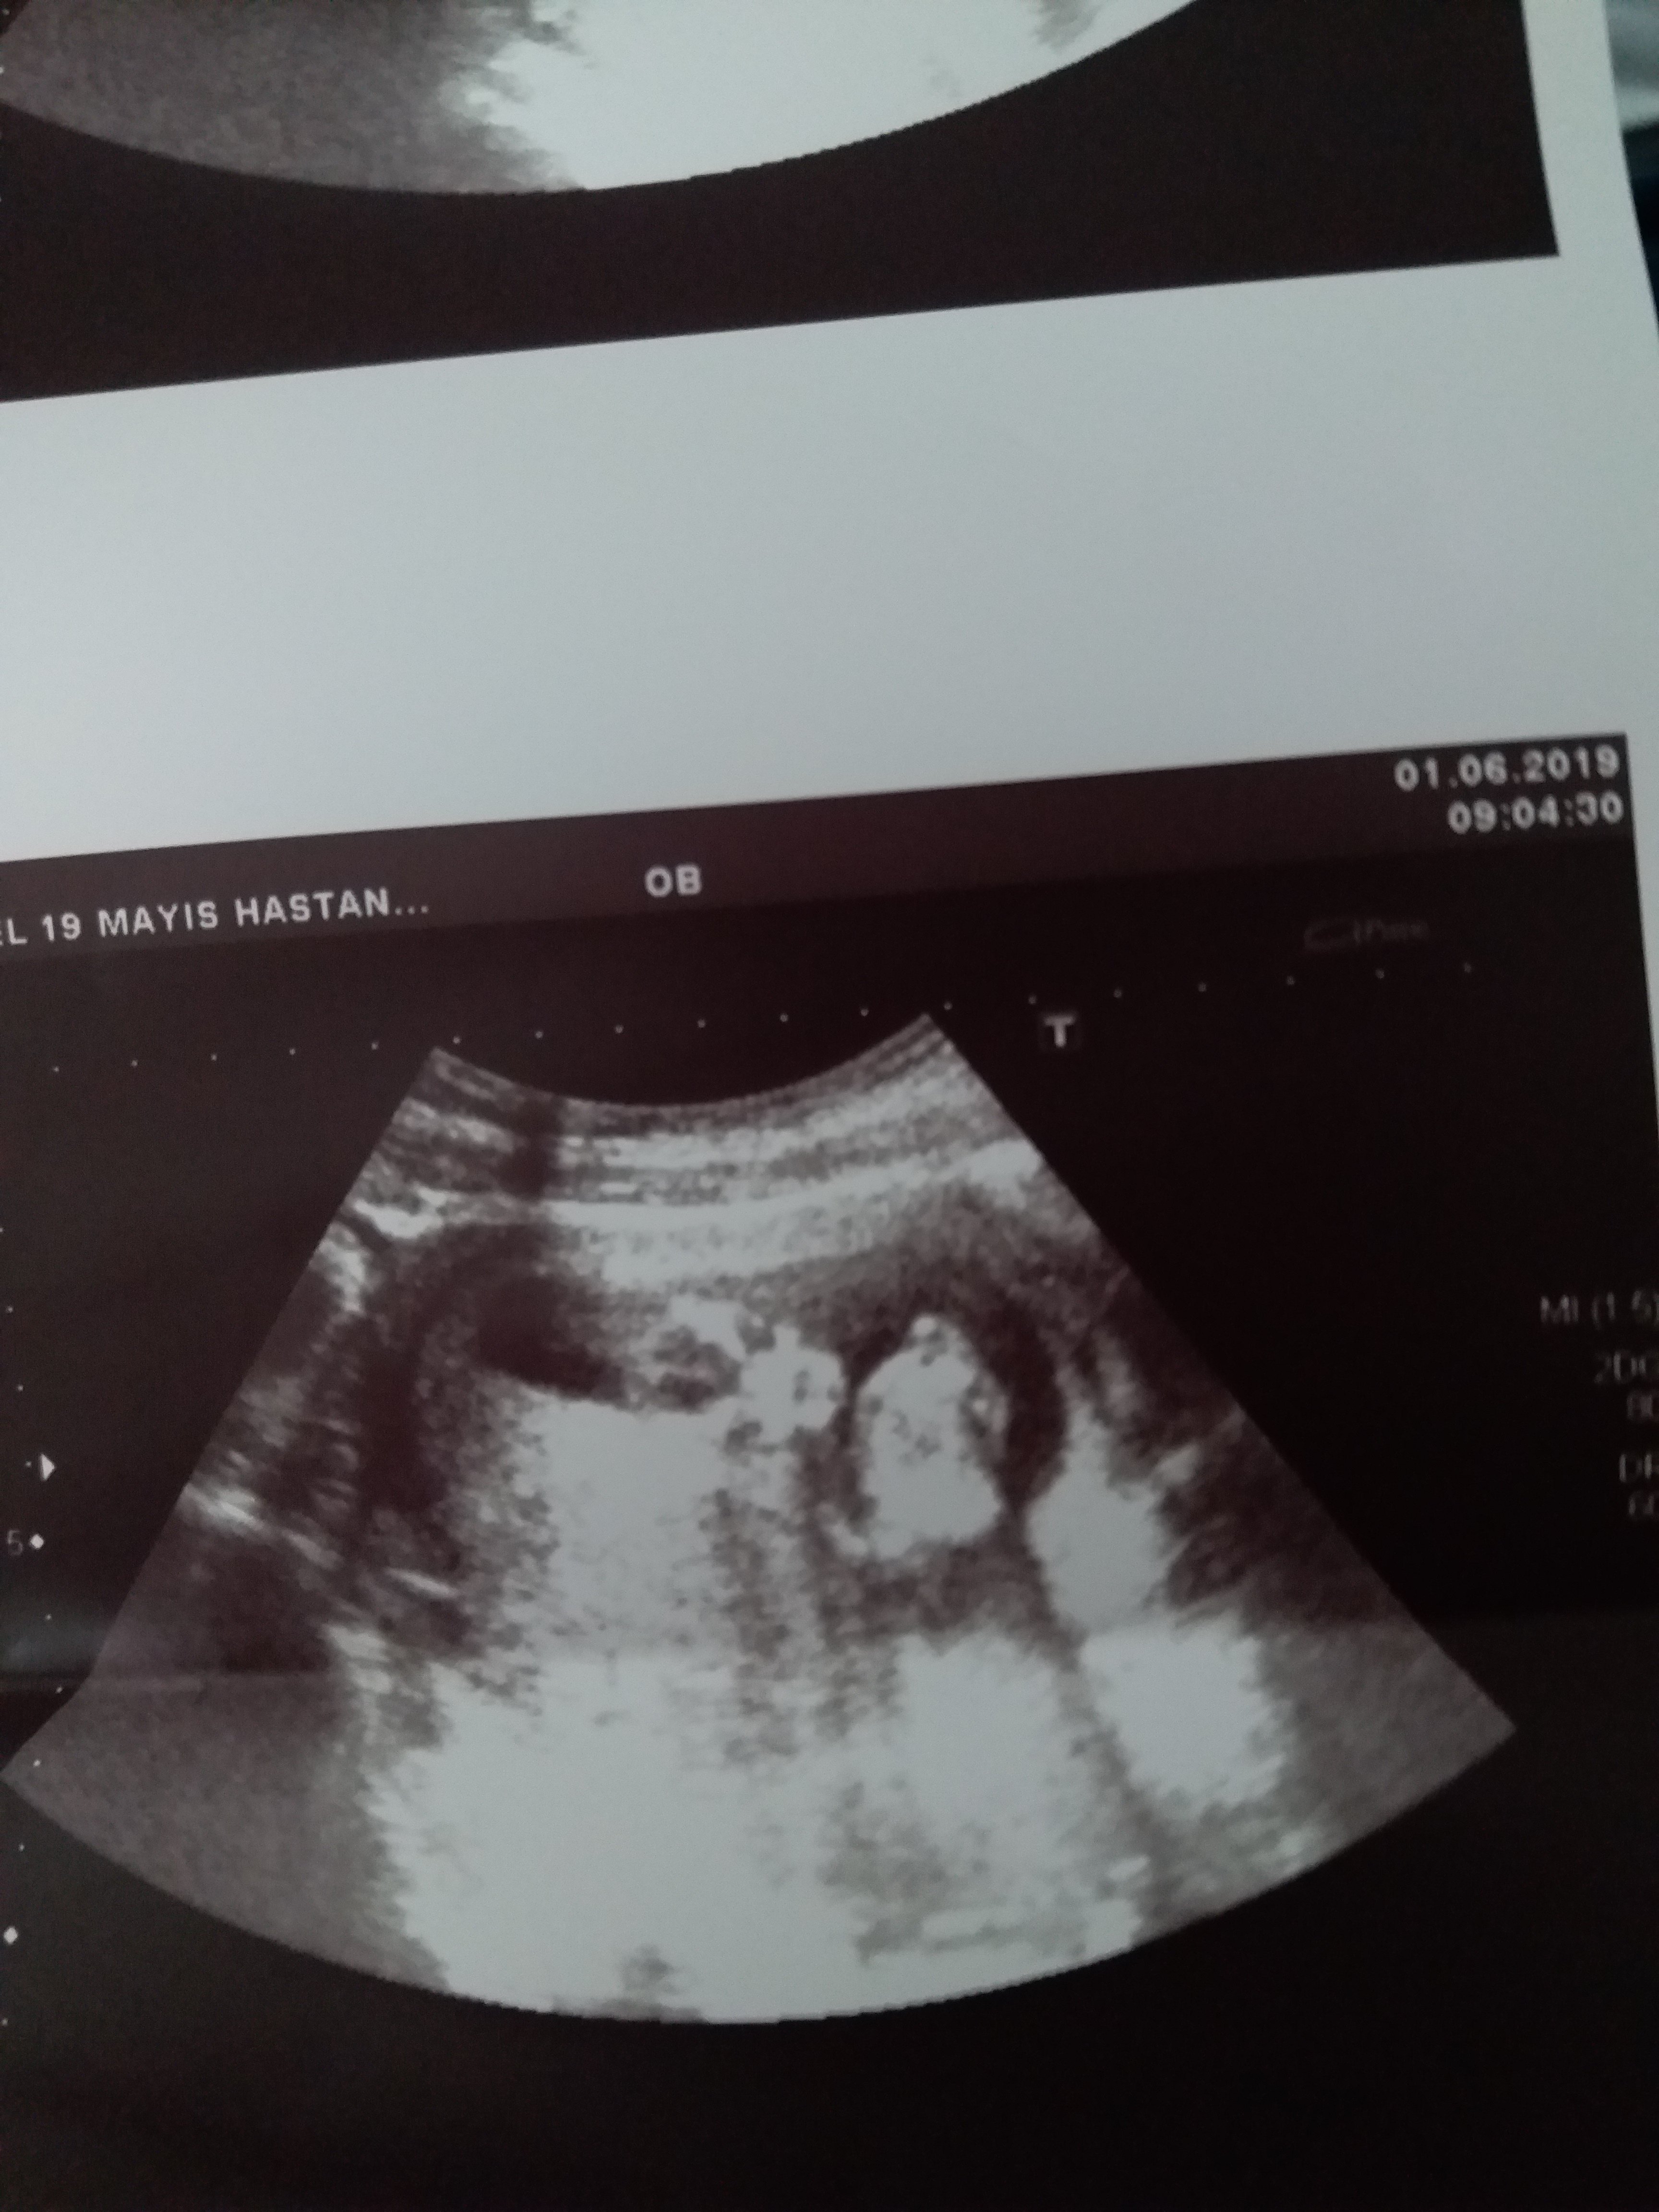

Sizce cinsiyet nedir ya bu hafta tekrar gittim doktora net konuşmadı 12 haftadayız lütfen bilen Allah rızası için yardımcı olsun

20190601_113841.jpg

20190601_113816.jpg